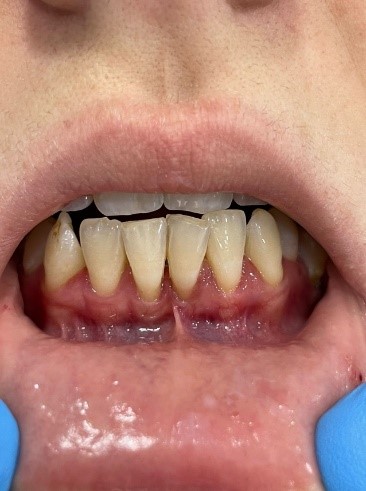

Клинический случай № 2. Пациентка 28 лет находится на ортодонтическом лечении. Пришла на прием по рекомендации врача-ортодонта. Осмотр преддверия полости рта показал недостаточное количество прикрепленной десны во фронтальном отделе нижней челюсти. Констатировано мелкое преддверие полости рта, 3 мм прикрепленной десны (рисунок 3a). Рекомендовано углубление преддверия путем вестибулопластики. Сопутствующие соматические заболевания отрицает. Результаты общего анализа крови без видимых патологий.

Проведена операция по углублению преддверия полости рта по Эдлану – Мейхеру. Рассечение и смещение мышечных тяжей апикально (рисунок 3b). Наложение швов с фиксацией слизистого лоскута к надкостнице (рисунок 3c). После снятия швов даны рекомендации (рисунок 3d).

a

b

c

d

Рис. 3. Мелкое преддверие полости рта: a – мелкое преддверие; b – смещение мышечных тяжей апикально; c – фиксация слизистого слоя к надкостнице; d – углубленное преддверие полости рта

Fig. 3. Small Oral Vestibule: a – small vestibule; b – pical displacement of muscle strands; c – fixation of the mucous layer to the periosteum; d – the deepened vestibule of the oral cavity

Вестибулопластика по Эдлану – Мейхеру наших пациентов позволила увеличить объем прикрепленной десны до 1 см. Смещение мышечных тяжей во фронтальном отделе сняло нагрузку с маргинального пародонта. И в первом, и во втором клиническом случае при оттягивании нижней губы признаки ишимизации исчезли. Жалобы на чувство дискомфорта в области нижних резцов исчезли. Вовремя проведенное углубление преддверия полости рта позволило стабилизировать состояние пародонта.